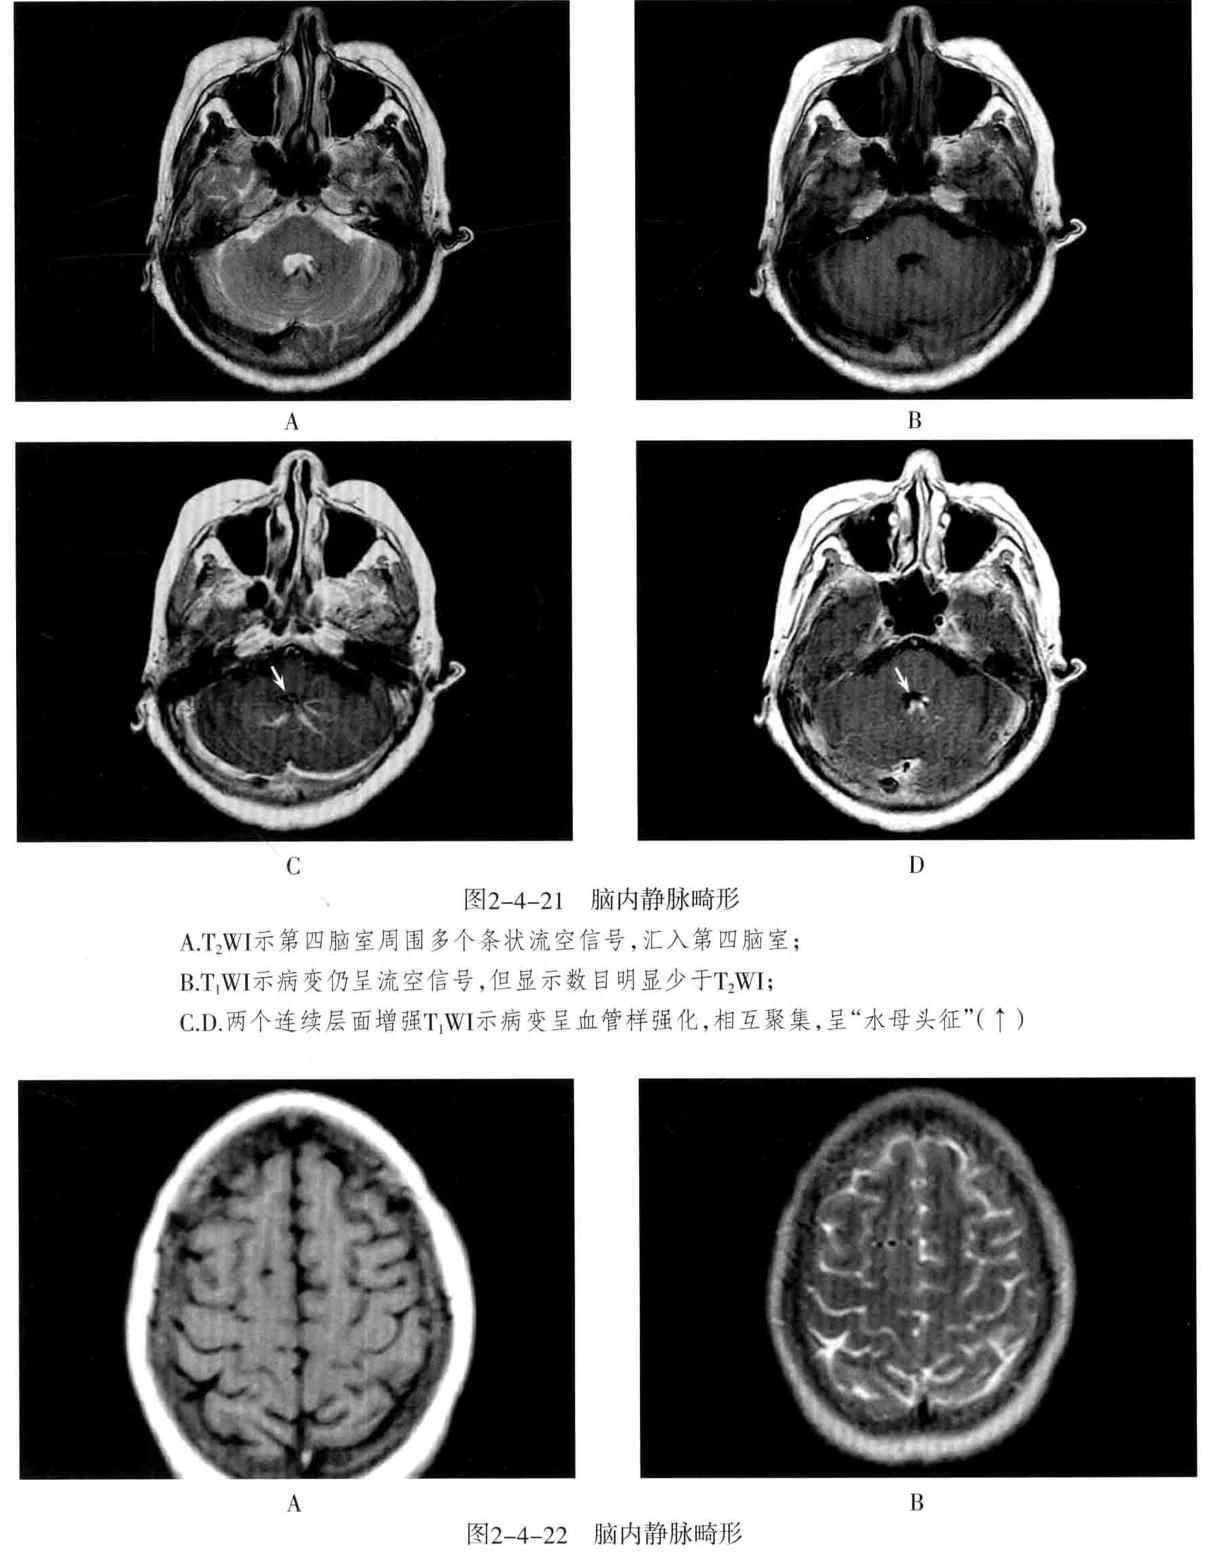

- MRI检查:T1WI多呈高信号、稍高信号或混杂信号,T2WI上呈高、低混杂信号,典型者呈“爆米花”状,境界清楚,病灶周围有含铁血黄素沉积,T2WI是表现为低信号环。病灶内及周边无流空血管影。病灶无占位效应,周围脑组织无水肿。大量出血时,表现为病灶短期明显增大,可有占位效应。增强后脑内者病灶可轻度强化,亦可无强化。脑外者多于颅底鞍旁,T1WI低信号,T2WI明显高信号,边界清楚,增强后明显强化且强化均匀。

- 脑静脉性血管瘤 极为少见。静脉性血管瘤是一种组织上完全由静脉成分构成的脑血管畸形,任何年龄均可见,病理特点为许多放射状排列的扩张髓静脉连接成一条或多条扩张的经皮质或室管膜下引流静脉,最后汇入静脉窦。常发生于 额叶及小脑,以第四脑室周围多见 ,常伴发其他血管畸形,最常见为海绵状血管瘤。

- CT表现:平扫显示不清,周围无脑水肿,有时可见出血等改变,CTA典型表现为额叶或小脑许多细小髓静脉放射状汇入一条或几条引流静脉,最后汇入静脉窦,呈“水母头征”。

- MRI表现:可因病灶大小及血流速度不同而在MRI上呈多种信号,T1WI、T2WI多呈流空信号,少数由于血流缓慢也可呈略高信号,FLAIR呈低信号。增强后髓静脉及引流静脉明显强化,典型者呈“水母头征”,引流静脉可走向脑表面而引流至静脉窦,或走向脑室引流至室管膜静脉。MRV可显示引流静脉及其引流情况,但不显示髓静脉,SWI序列对本病显示很敏感。病灶周围无脑水肿表现,有时可见出血。